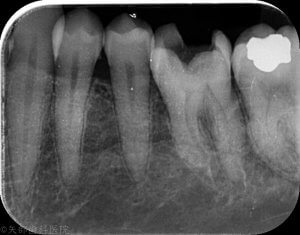

強い自発痛で来院された患者さん。歯がズキズキうずいて夜もなれなかったそうです。口腔内所見では原因歯に大きな虫歯によるう窩が認められ、レントゲン所見では透過像が歯髄腔まで及んでいます。典型的な不可逆性歯髄炎ですね。